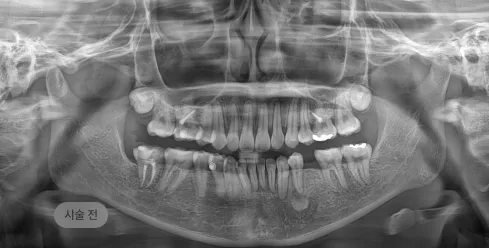

화면을 드래그하여 전/후를 비교해 보세요